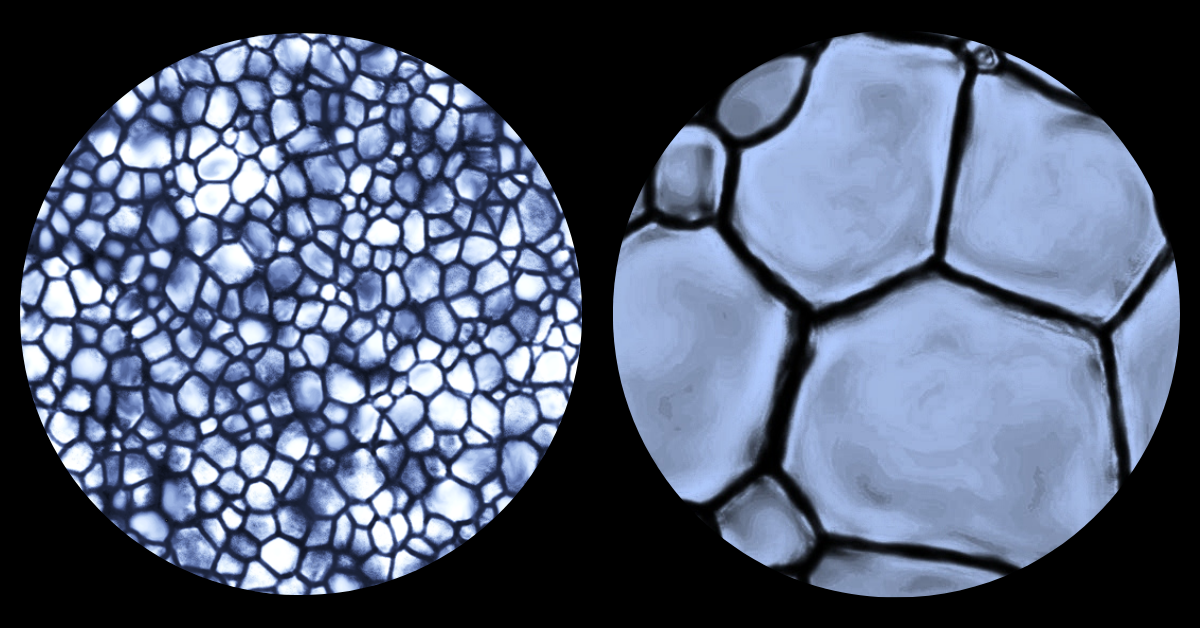

The growth of ice crystals on a microscopic scale

“Ice growth, or the process of ice recrystallization, is an inevitable side-effect of freezing something and over time, and with temperature fluctuations, ice crystals become larger and larger and cause a lot of disruption in cell membranes, which in turn damages or kills the cells.

"Small ice crystals are innocuous but large ice crystals damage cell membranes easily. These small crystals are like grains of sand on a Caribbean beach which are so small that they mould to your body and you can lay comfortably on the beach for an entire day. Now, let’s say those grains of sand were replaced by gravel or pebbles. That’s a lot less comfortable. Our cryopreservation technology prevents ice crystals from growing (and thus remain small) during freezing and thawing ensuring the survival of cells."